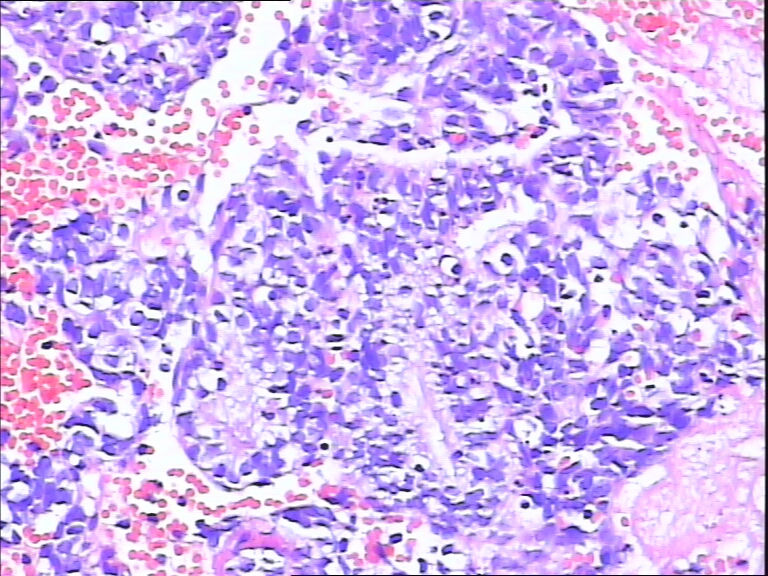

41岁,停经5年再出血。

• 宫内膜图1

图1

流血期子宫内膜,腺体反应不同步

腺体反应不同步,部分增生期改变,部分上皮细胞有核下空泡呈早分泌期改变,是用过药物?

片子不是很清楚,像是月经期子宫内膜

流血期子宫内膜,腺体反应不同步。

腺体增生,部分腺上皮有分泌。